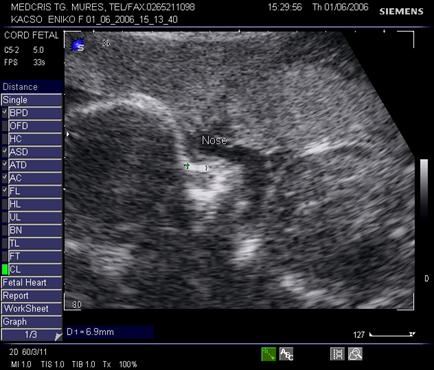

Fig. nr. 280. Formatiune anecogena intrabdominala, posibil hidronefroza , la un fat cu anamnios, retard major de crestere intrauterina RCIU si presupus sindrom genetic

Fig. nr. 281. Acelasi fat cu anamnios si RCIU, cu os nazal relativ scurt